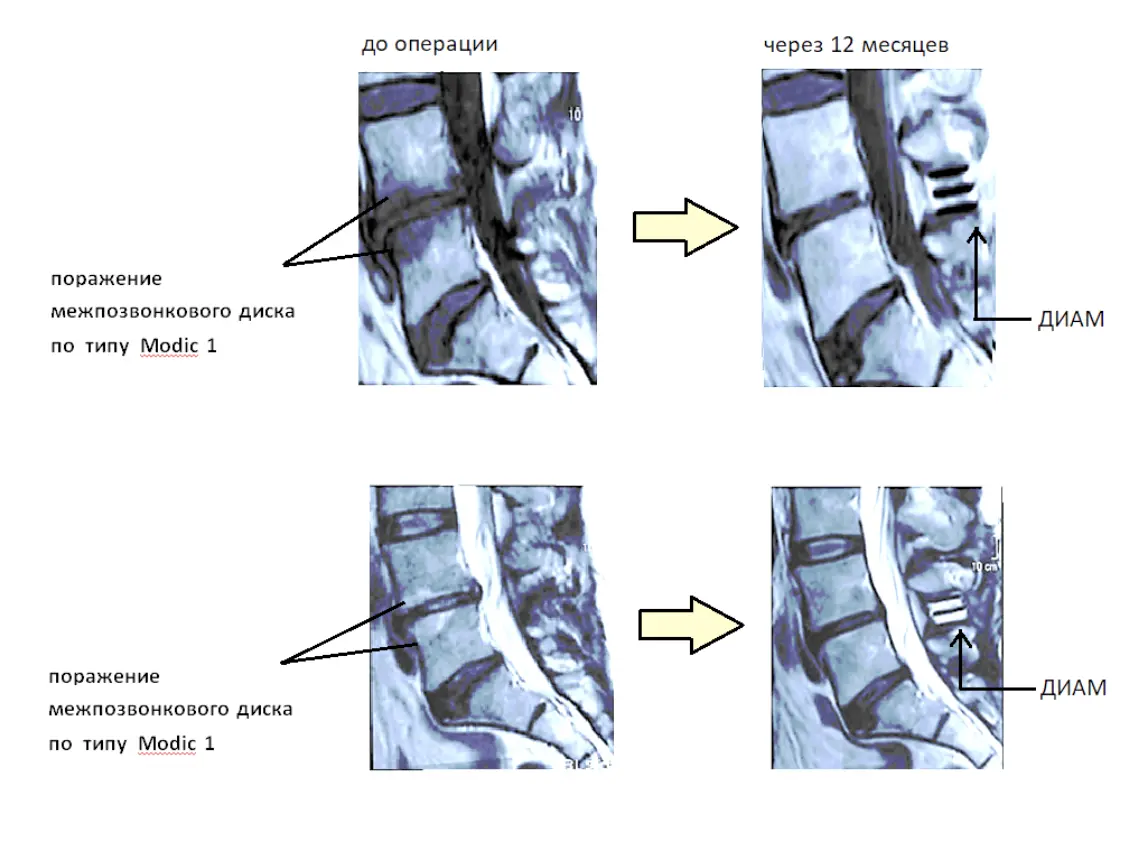

7. При дискогенной боли в поясничном отделе позвоночника когда боли в спине, связаны с поражением межпозвонкового диска. Изолированные поражения МПД с изменением сигнала по типу Modic 1 – синдром «черного диска».

Примеры применения динамического имплантата ДИАМ

Использование динамической межламинарной стабилизации после декомпрессивных операций позволяет замедлить или остановить развитие дегенеративного процесса на оперируемом уровне и избежать развитие послеоперационной нестабильности. В 30% происходит регенерация пораженного межпозвонкового диска. В отдаленном периоде жизни пациентов их работоспособность и качество жизни в целом существенно выше, чем у тех пациентов, которым была выполнена операция без использования имплантата или у пациентов которым выполнена жесткая стабилизация.